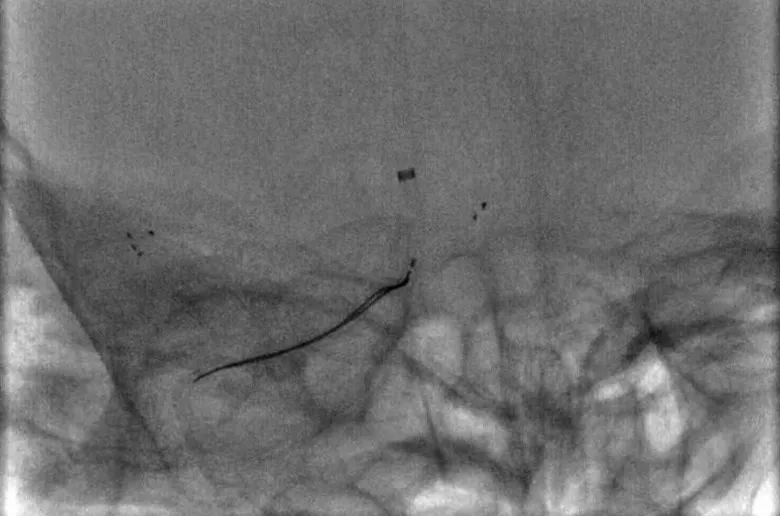

8F指引导管联合6F Navien中间导管,右侧MCA取栓:微导丝到位;Rebar27导管到位,冒烟证实于血管腔内;6*30mm支架放置MCA-M1段,MCA未见显影,ACA未见显影;表明血栓负荷非常大

8F指引导管联合6F Navien中间导管,右侧ACA取栓:微导丝到位;Rebar18导管到位,冒烟证实于血管腔内;Solitaire 4-20支架放置ACA-A1分支内